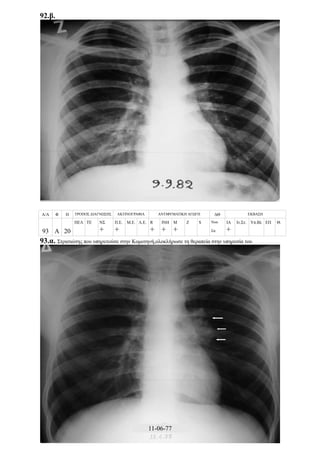

Περίπτωση 24η:

Α/Α Φ Η ΤΡΟΠΟΣ ΔΙΑΓΝΩΣΗΣ ΑΚΤΙΝΟΓΡΑΦΙΑ ΑΝΤΙΦΥΜΑΤΙΚΗ ΑΓΩΓΗ ΔΘ ΕΚΒΑΣΗ

24 Α 14

ΠΕΛ ΤΕ ΝΣ

+

+ ++ +++

R

ΙΝΗ

Μ

Z S Νοσ.

Σπ.14

ΙΑ

Ιν.Στ. Υπ.Βλ ΕΠ Θ.

24.α.

24.β.